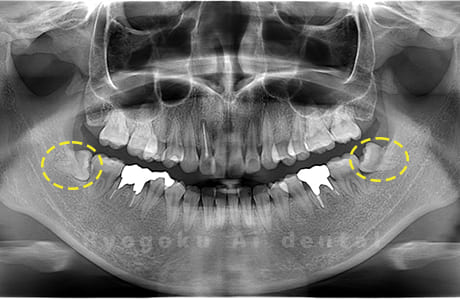

Case01

- 原因

- 水平埋伏智歯

- 治療内容

- 下顎の水平埋伏智歯を抜歯

<リスク・副作用>

手術後は痛み、腫れ、痺れなどの副作用が生じる場合があります。